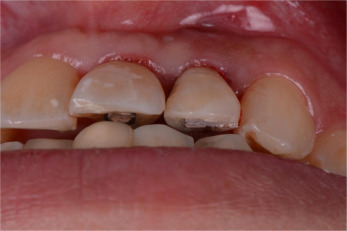

Fig. 4.

(a) Labial view of soft tissue healing 6 weeks after IIPIP of central incisor. (b) Screw access hole on the palatal surface of implant supported natural crown of left central incisor.